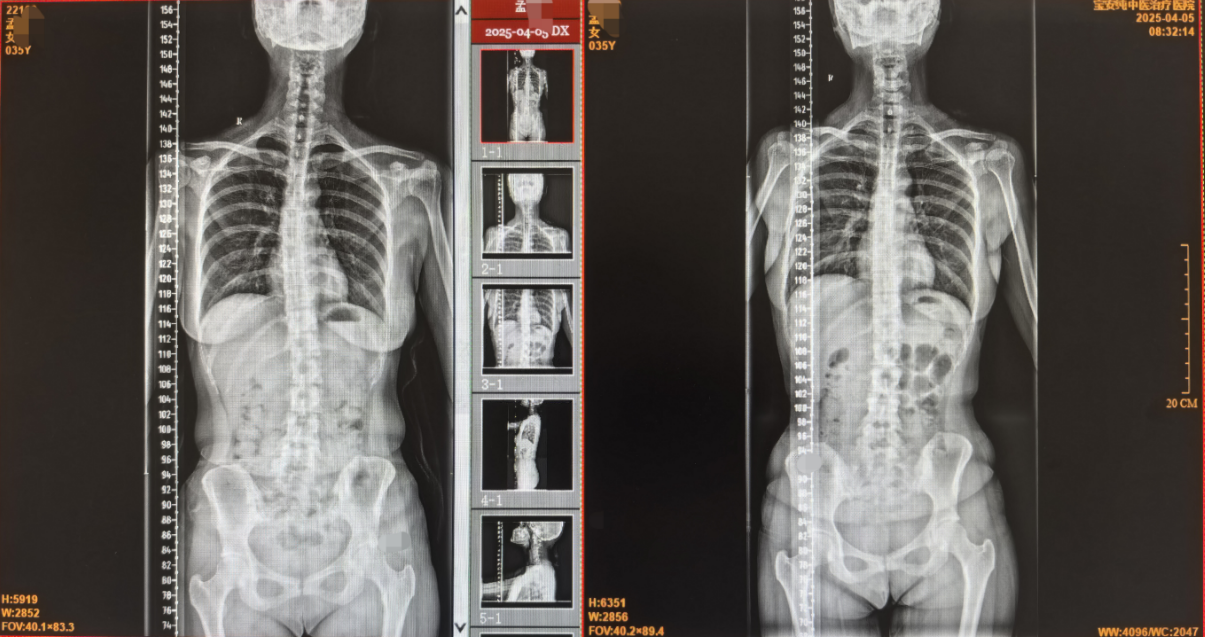

体征:可触及胸3-胸7脊柱向右侧歪斜,左侧胸3-胸7、腰1-腰3可触及明显紧张竖脊肌肌肉条索,压痛剧烈。

4月05日治疗多次后复查片子:

治疗前后对比:

一般来说,脊柱侧弯的保守治疗是比较困难的,因为涉及需要调整的部位很多,比如颈椎、腰椎、胸椎等等,治疗难度大、耗时长且效果不一定明显,所以对于该病,除非是年轻人侧弯比较典型且出现明显的颈、腰、背部等不适症状,一般轻微的脊柱侧弯可不行治疗干预,嘱患者改变不良生活习惯,适量运动即可。症状明显的可以进行治疗,但一般不以完全纠正侧弯为目的,主要目标为改善不适症状为主。该患者就诊的主诉为腰背部疼痛,诉求为主要缓解疼痛、尽量纠正侧弯,患者比较有耐心,前前后后在我处共治疗了两个多月合计20余次手法正骨及针灸治疗,复查片子可见效果明显,虽骨盆处仍有歪斜,但症状较就诊前大大改善。